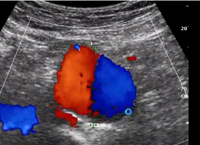

Ecodoppler de Colorido de Aneurisma Aórtico

• from Franco Accorsi

• Setembro. 2013

Ecodoppler Colorido de Aneurisma Aórtico